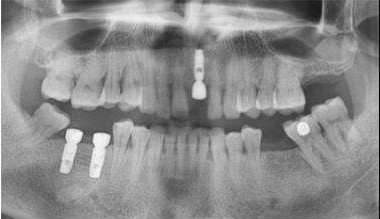

CBCT拍攝,進(jìn)行牙槽骨厚度、寬度和高度的測(cè)量。

檢查需拔除的牙根,判斷是否符合種植的條件。

根絕骨質(zhì)量的情況,提前選擇是否需要數(shù)字化種植導(dǎo)板。